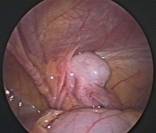

Acute Scrotum

Acute scrotum is sudden onset of redness and swelling over the scrotum. This is associated with severe pain over the scrotum and sometimes lower abdomen and may be accompanied with nausea and vomiting.

Of the many causes of acute scrotum, the most common and important is Torsion of Testis. The testis is supplied by a single blood vessel and any torsion on this vessel may impede the blood supply to the testis. If urgent medical attention and intervention is not done, this may result in testicular gangrene and orchidectomy ( removal of the dead testis) may be needed.